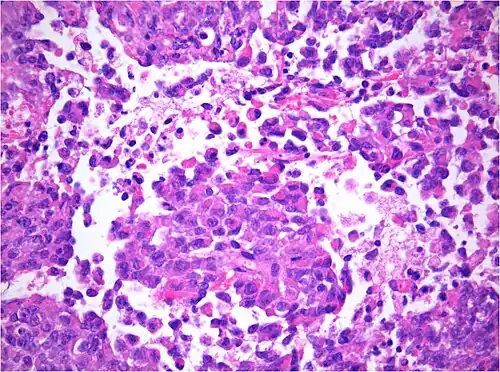

AT/RT and rhabdoid tumor share the term "rhabdoid" because under a microscope, both tumors resemble rhabdomyosarcoma.

Histology

The tumor histopathology is jumbled small and large cells. The tissue of this tumor contains many different types of cells including the rhabdoid cells, large spindled cells, epithelial and mesenchymal cells, and areas resembling primitive neuroectodermal tumor (PNET). As much as 70% of the tumor may be made up of PNET-like cells. Ultrastructure characteristic whorls of intermediate filaments are seen in the rhabdoid tumors (as with rhabdoid tumors in any area of the body). Ho and associates found sickle-shaped embracing cells, previously unreported, in all of 11 cases of AT/RT.[24]

Immunohistochemistry for INI1, the product of the SMARCB1 gene typically defective in AT/RT: Note the loss of brown staining in the nuclei of tumor cells with defective SMARCB1 as compared to retained staining of nuclei of vascular cells (internal positive control).